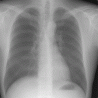

Seit der Entdeckung der Röntgenstrahlen und ihres Wertes für die Medizin hat sich an der Technik vieles geändert. Unter anderem wird in unserer Praxis nicht mehr auf fotographischen Film belichtet. Stattdessen kommen strahlensensiblere Fluoreszenzspeicherfolien zur Anwendung, von denen die Bilder mit einem Laserstrahl digital ausgelesen werden.

An der wichtigen Rolle der Röntgendiagnostik, vor allem im Bereich von Lunge und Skelettsystem hat sich indessen nichts geändert. Zahlreiche Spezialuntersuchungen haben sich im Laufe der Jahrzehnte herausgebildet. Das technisch am höchsten entwickelte Röntgenverfahren stellt die Computertomographie (CT) dar.